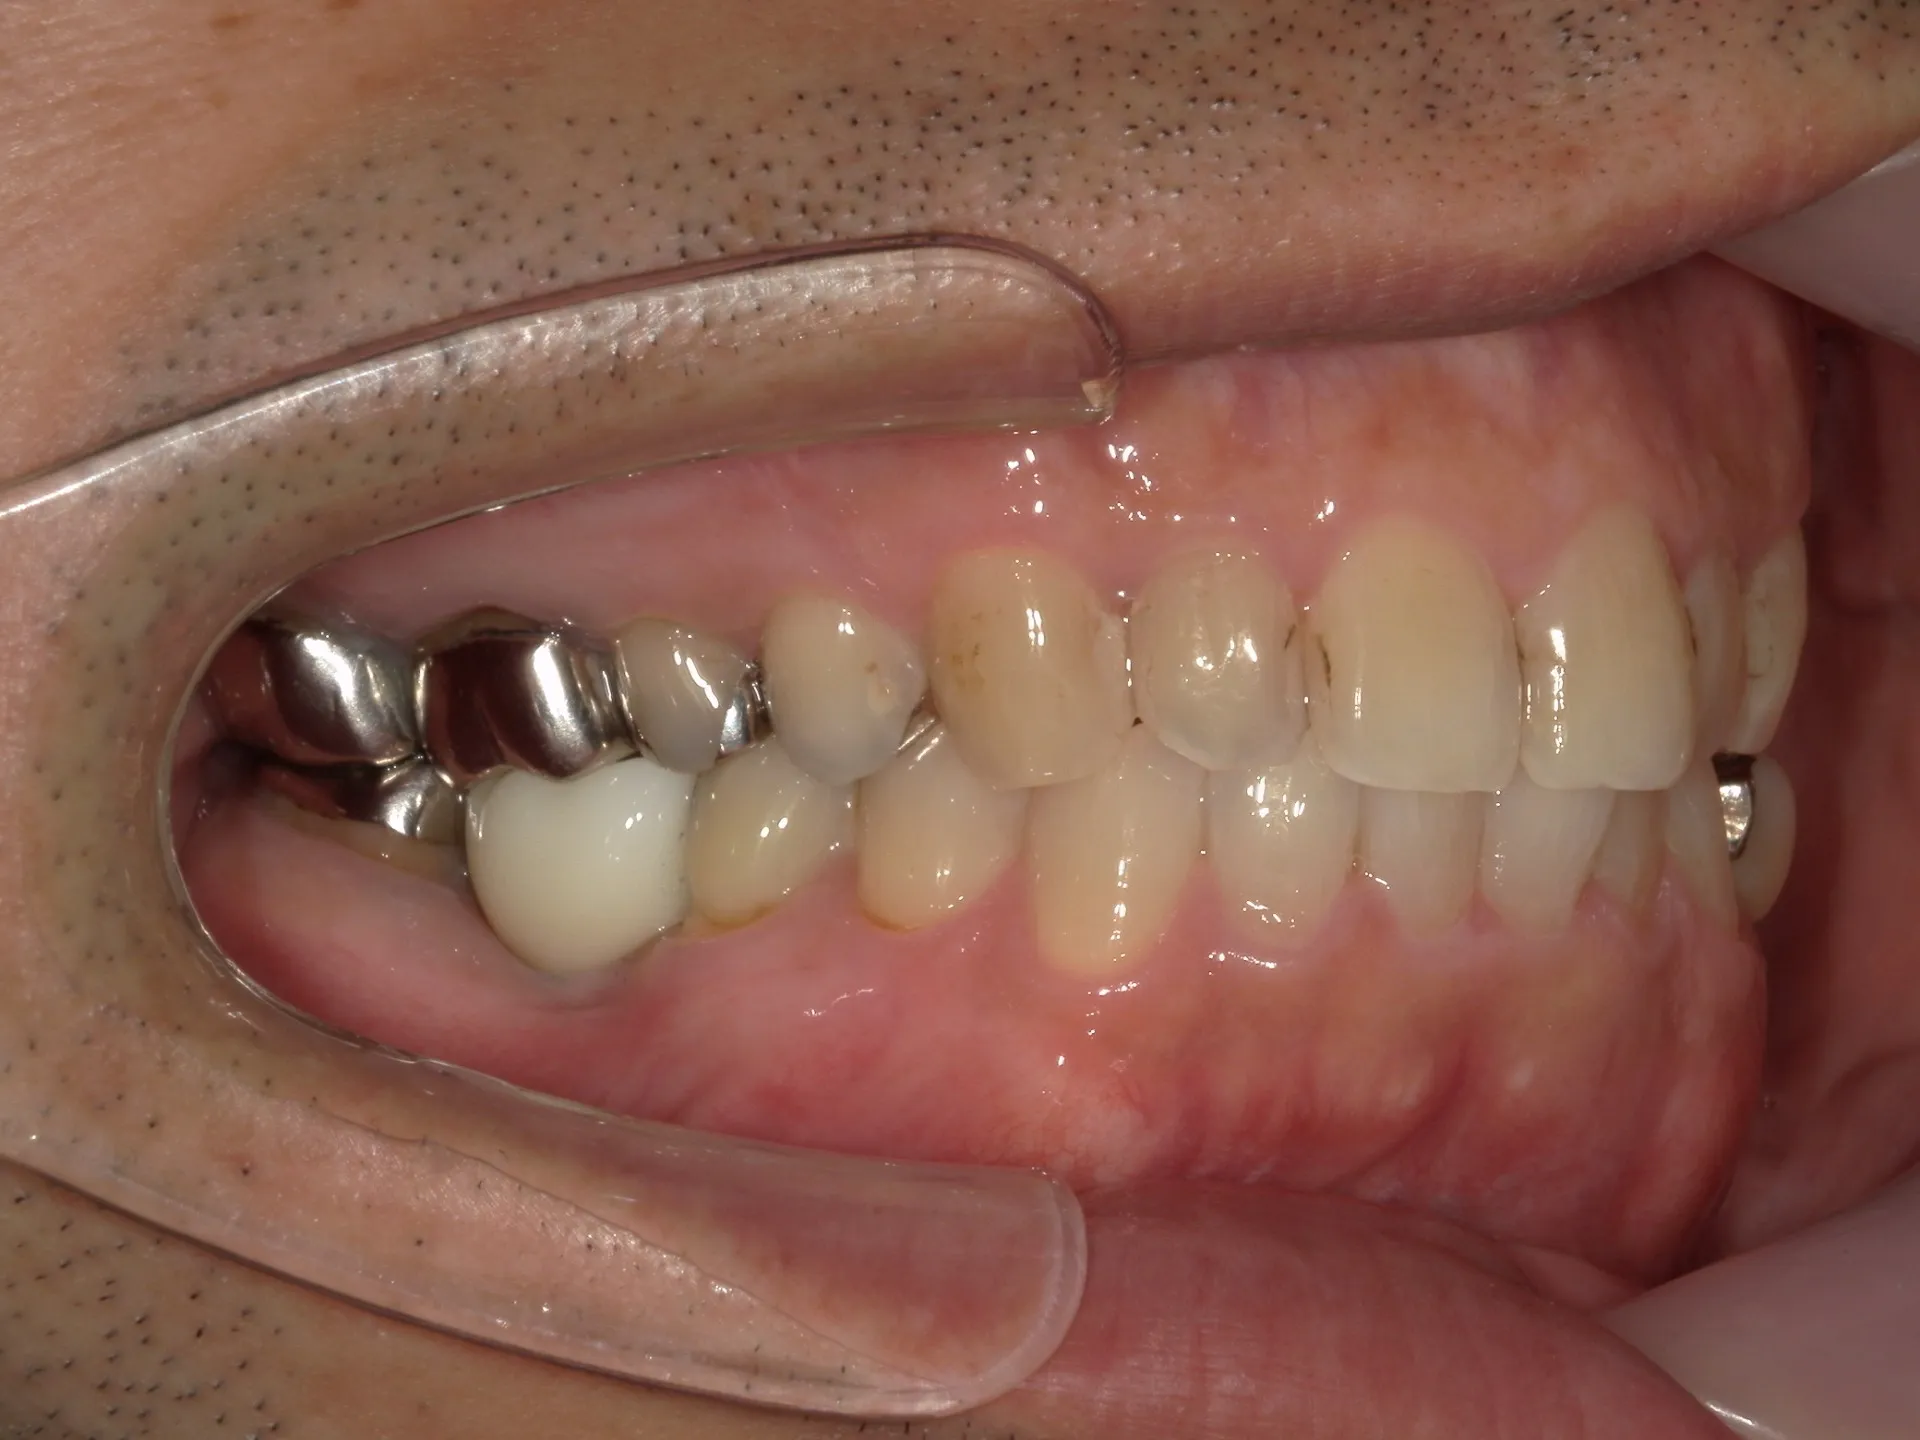

今回は抜歯になってしまった歯からインプラント治療完了までの流れについてご紹介いたします。